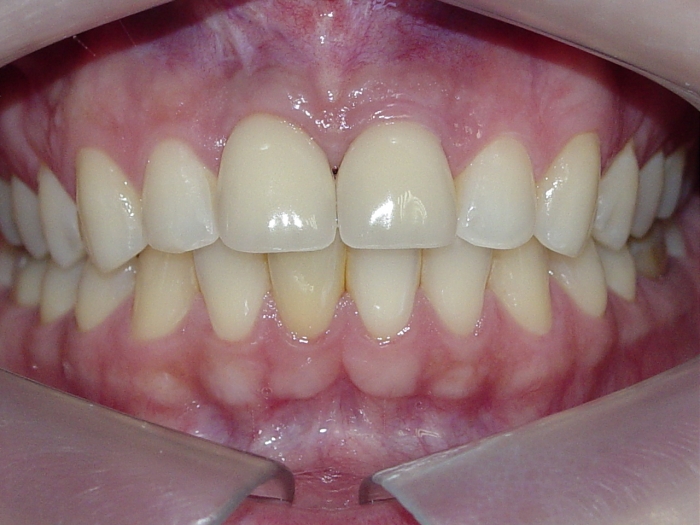

Próteses provisórias imediatas nos elementos 11 e 21